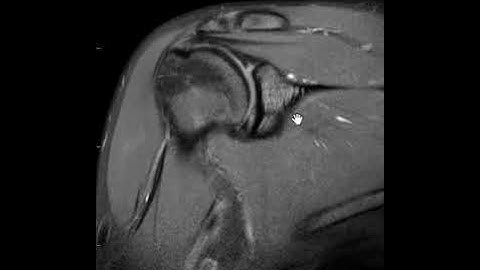

What It’s Like to Get an MRI Arthrogram